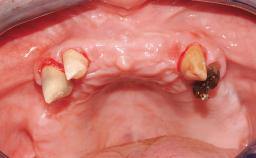

Immediate Loading of Eight Implants in the Maxilla and Six Implants in the Mandible and Final Restoration with Three-Unit and Four-Unit FDPs

German Gallucci, Jean-Pierre H Bernard, Urs C Belser

Extensive scientific evidence has confirmed that immediately loaded implants with fixed full-arch provisional restorations can osseointegrate with success rates similar to conventionally or delayed loaded implants. A number of immediate-provisionalization techniques for edentulous jaws have been described. Some protocols differ when it comes to prefabricated provisional templates versus complete denture conversion; intrasurgical impressions versus direct relining; and cemented versus screw-retained provisional restorations. In this context, complete-denture conversion has been proposed for either intrasurgical impressions or direct relining. Another possibility is the utilization of a prefabricated provisional to be adapted either in the mouth (by direct relining) or in the laboratory (on a working model obtained from an intrasurgical impression).